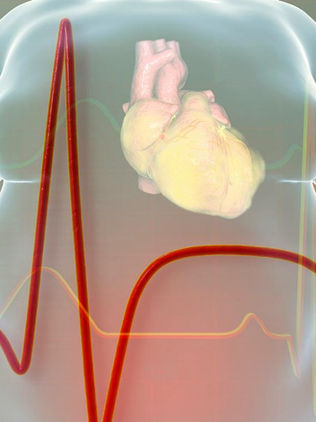

Veneno de abeja: qué es y para qué sirve

El veneno de abeja, también conocido como apitoxina, ha pasado de ser únicamente el causante del dolor tras una picadura a convertirse en un objeto de estudio prometedor en la medicina moderna. En los últimos años, su posible aplicación en tratamientos contra la artritis, enfermedades autoinmunes e incluso algunos tipos de cáncer ha despertado el interés de laboratorios, universidades y la industria farmacéutica. ¿Qué contiene el veneno de abeja? El veneno de abeja es una sus